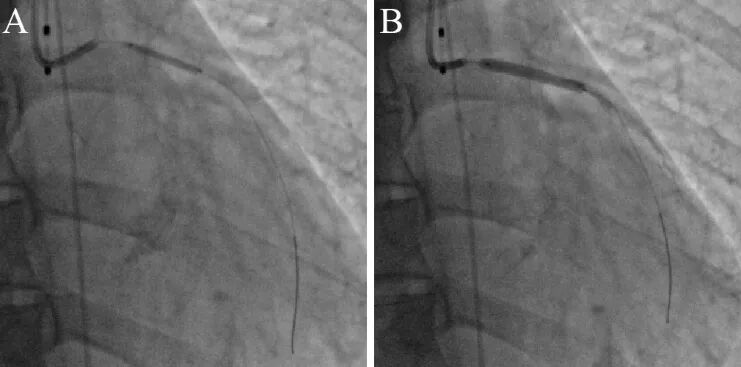

2、首次冠脉造影

冠脉造影示严重三支开口病变:左主干狭窄80%,累及前降支开口狭窄99%,回旋支开口狭窄90%,右冠开口狭窄90%(图1)。

图1冠状动脉造影显示严重三支开口病变,箭头示狭窄部位

3、复查冠脉造影

10年后患者胸闷症状似有反复,活动后稍气促,程度较轻,休息或含服硝酸甘油后缓解。入院复查造影。

冠脉造影示三支冠脉无狭窄(图2),LIMA桥血管纤细。对比10年前造影,开口狭窄几乎消失(图3)!最合理的解释是,原先狭窄为导管诱发冠脉开口严重痉挛!出院加用贝尼地平抗痉挛治疗,未有胸闷再发。

图2 10年后冠状动脉造影显示三支基本正常

图3 两次造影图像对比,箭头示狭窄部位